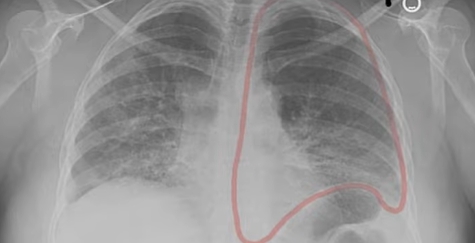

폐 섬유증이란 한 번 손상되면 회복이 어려운 진행성 폐 질환입니다. 하지만 조기에 발견해 치료를 시작하면 진행 속도를 늦추고 삶의 질을 유지할 수 있습니다.

✔ 흉부 CT에서 이상 소견이 나온 경우

이 중 하나라도 해당된다면 호흡기내과 진료를 통해 정확한 평가가 필요합니다. 폐 섬유증은 막연히 두려워할 병이 아니라, 정확히 알고 조기에 관리해야 하는 질환입니다. “나이 탓이겠지”라는 생각이 진단 시기를 늦추는 가장 큰 원인이라는 점을 꼭 기억하시기 바랍니다.